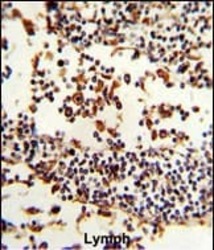

Immunohistochemistry

PA5-14361 IHC